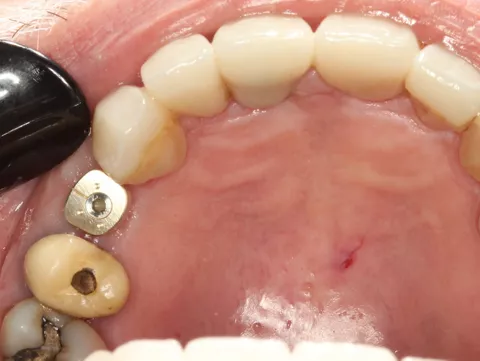

For the maxillary single‑tooth implant, a fully digital guided workflow was used, allowing a flapless approach. Soft‑tissue access was achieved with a tissue punch through the surgical guide [5], followed by osteotomy preparation using the Axiom® X3 drilling protocol. The implant achieved high primary stability (≈50 N·cm), enabling immediate placement of a HealFit® SH without suturing.

11a. 11b. 11c. 11d. Flapless guided placement of the maxillary implant with tissue‑punch access, Axiom X3 osteotomy, and immediate HealFit® SH placement without sutures.

11a

11b

11c

11d